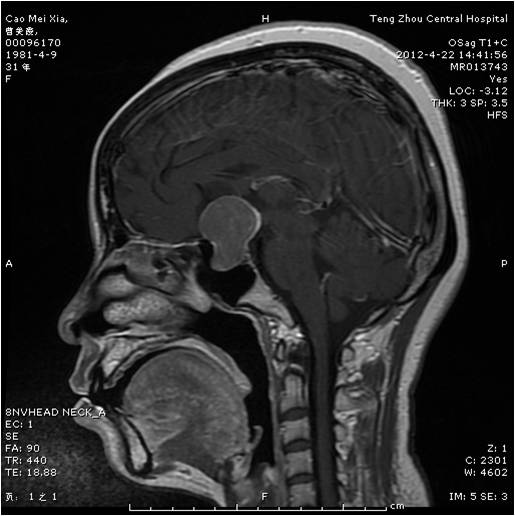

垂體瘤術(shù)前 垂體瘤術(shù)后